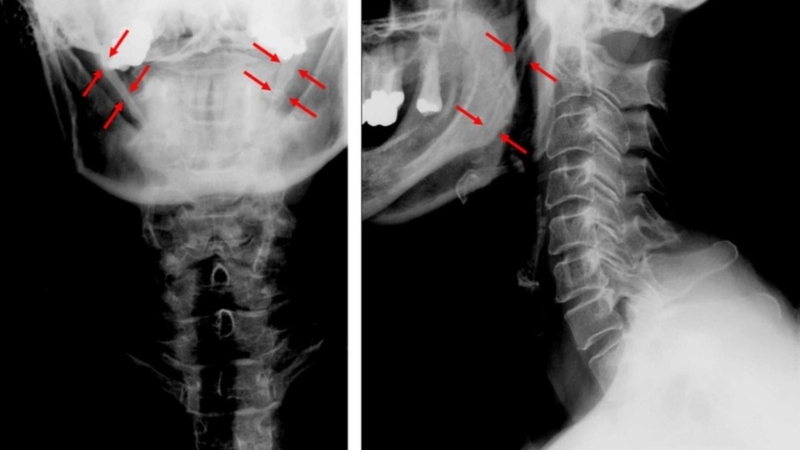

Biểu hiện của dài mỏm trâm và những phương pháp điều trị 2

Dài mỏm trâm trên X-quang